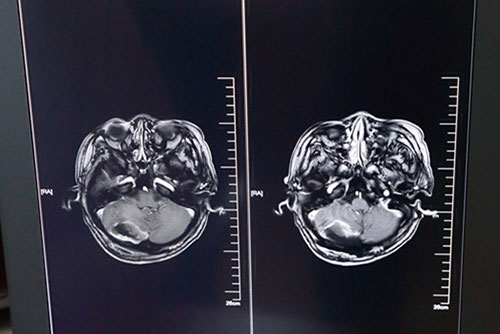

神笔有马良,神手有侯主任。手术室内,无影灯下,切开、上显微镜、颅脑手术导航系统导航.....手持手术器械的侯主任神态专注,娴熟地进行每一个手术步骤,严格按照边界尽量多的精准切除肿瘤物。不到4个半小时,手术顺利结束,肿瘤基本全切,重要脑组织及颅神经血管保留完整。术后一月余,欧女士顺利出院,头痛、走路不稳等症状明显改善。

欧女士术后头颅MRI影像资料:肿瘤物消失